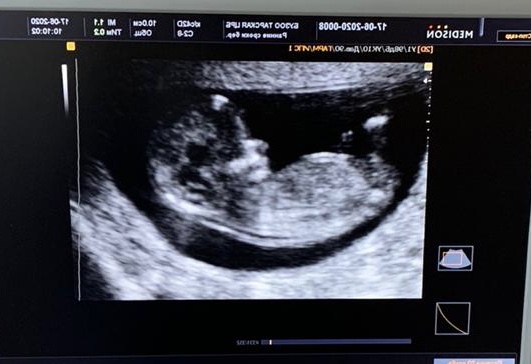

Подтвердили пол🥰💙

Пол малышаУ нас будет мальчик! Подтвердили пол и девочки вы тоже угадали! У нас сейчас 21 неделя. Думаю не должно быть ошибки уже) Как думаете можно вещички покупать?

Тут нам 13 недель))

Тут даже по лицу на снимке видно, что мальчик! ☺️Думаю на таком сроке пипирка уже никуда не денется